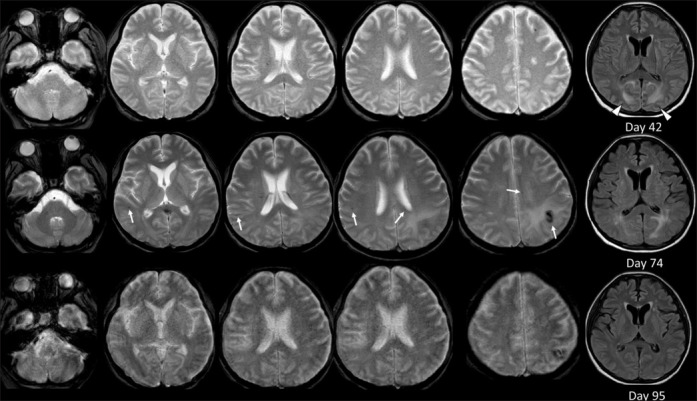

一例因多次外伤并发败血症和可逆性后遗白质脑病综合征以及迟发性多灶性微出血而遗留的痉挛性四肢瘫痪病例。

A Case of Spastic Quadriplegia Remaining after Multiple Traumatic Injuries Complicated by Sepsis and Reversible Posterior Leukoencephalopathy Syndrome, as well as Delayed Multifocal Microbleeds.